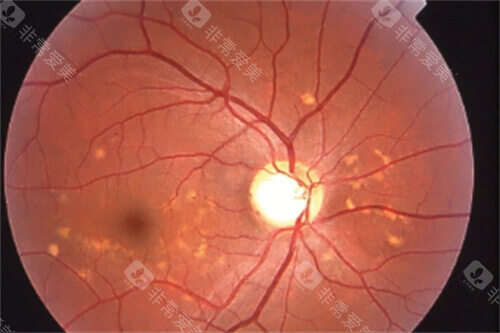

视网膜疾病:视网膜脱离、糖尿病视网膜病变、视网膜静脉阻塞等

实例二:42岁女性糖尿病患者,因"双眼视力逐渐下降"就诊。检查发现双眼严峻的糖尿病视网膜病变伴黄斑水肿。雷医生为其制定了系统的治疗方案,包括视网膜激光治疗和抗VEGF药物玻璃体腔注射。经过6个月治疗,患者视力稳定,黄斑水肿明显减轻。

对于糖尿病视网膜病变患者,通过系统治疗可使90%以上患者避免失明。